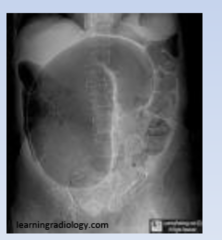

Volvulus

a loop of bowel twisting on itself. Etiology - may result from an ingested foreign body, adhesions or an unknown cause. Signs & Symptoms- vomiting, marked abdominal distention, severe abdominal pain. Diagnosis - AP, lateral & decubitus radiographs of the abdomen, barium enema. Shows SMOOTH TAPERED NARROWING Treatment - careful insertion of a sigmoidoscope can usually correct a volvulus in the sigmoid region

What types of radiographs should be taken for better visualization of a volvulus?

AP, lateral & decubitus radiographs of the abdomen